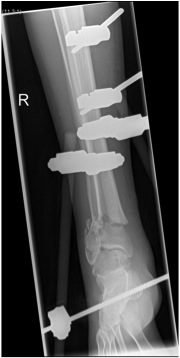

Temporary External fixation

Indications

- significant swelling

- significant displacement / non controlled in cast

- significant wounds, need for soft tissue coverage

Technique

- two pins proximal tibia

- trans-calcaneal pin

AO Trauma Ankle Bridging Delta Frame